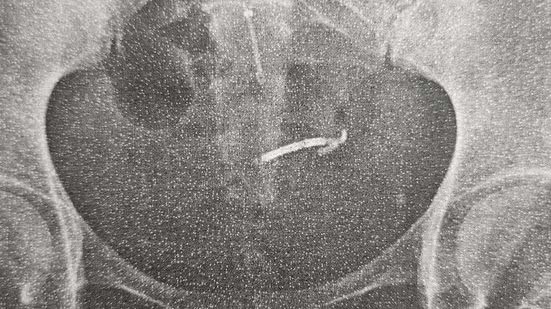

Três anos depois, um raio-x da bacia revelou algo inesperado. "Eu tenho escoliose e estava fazendo exames de acompanhamento. E foi nesse exame que apareceu a imagem do DIU — dos dois DIU's, na verdade, pois eu havia colocado um segundo dispositivo após ° parto do meu terceiro filho", disse. "Não tive nenhum sintoma nesses três anos, que me levasse uma desconfiança. Quando descobrimos, fizemos outros exames para saber a posição exata, e o dispositivo estava próximo ao intestino", revela.